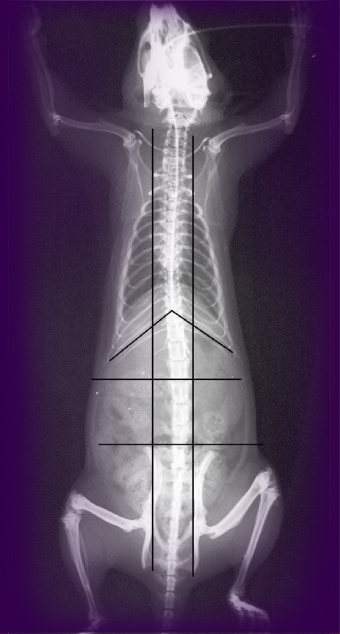

Tsafnat decided to test that accuracy by running a compression test on the very rat vertebra that she planned to model.

So Tsafnat placed her rat bone between two clamps in a compression chamber. The apparatus was small enough to fit in the University of Sydney’s newly purchased Micro-CT scanner, enabling her to scan the bone before and after it was put through its paces.

“We had the exact geometry, and all the boundary conditions were set up. Our only unknown was the material properties themselves,” says Tsafnat. The model bone was then squashed to reveal breaking points. Then the real bone was squashed until it really broke.

Thankfully, the experiment had a happy ending (though not, perhaps, for the rat bone . . . or the rat). Tsafnat’s model was dead on, validating the assumptions made for many a scanned bone of yesteryear. The fracture points it predicted were indeed the very places where the real bone fractured.